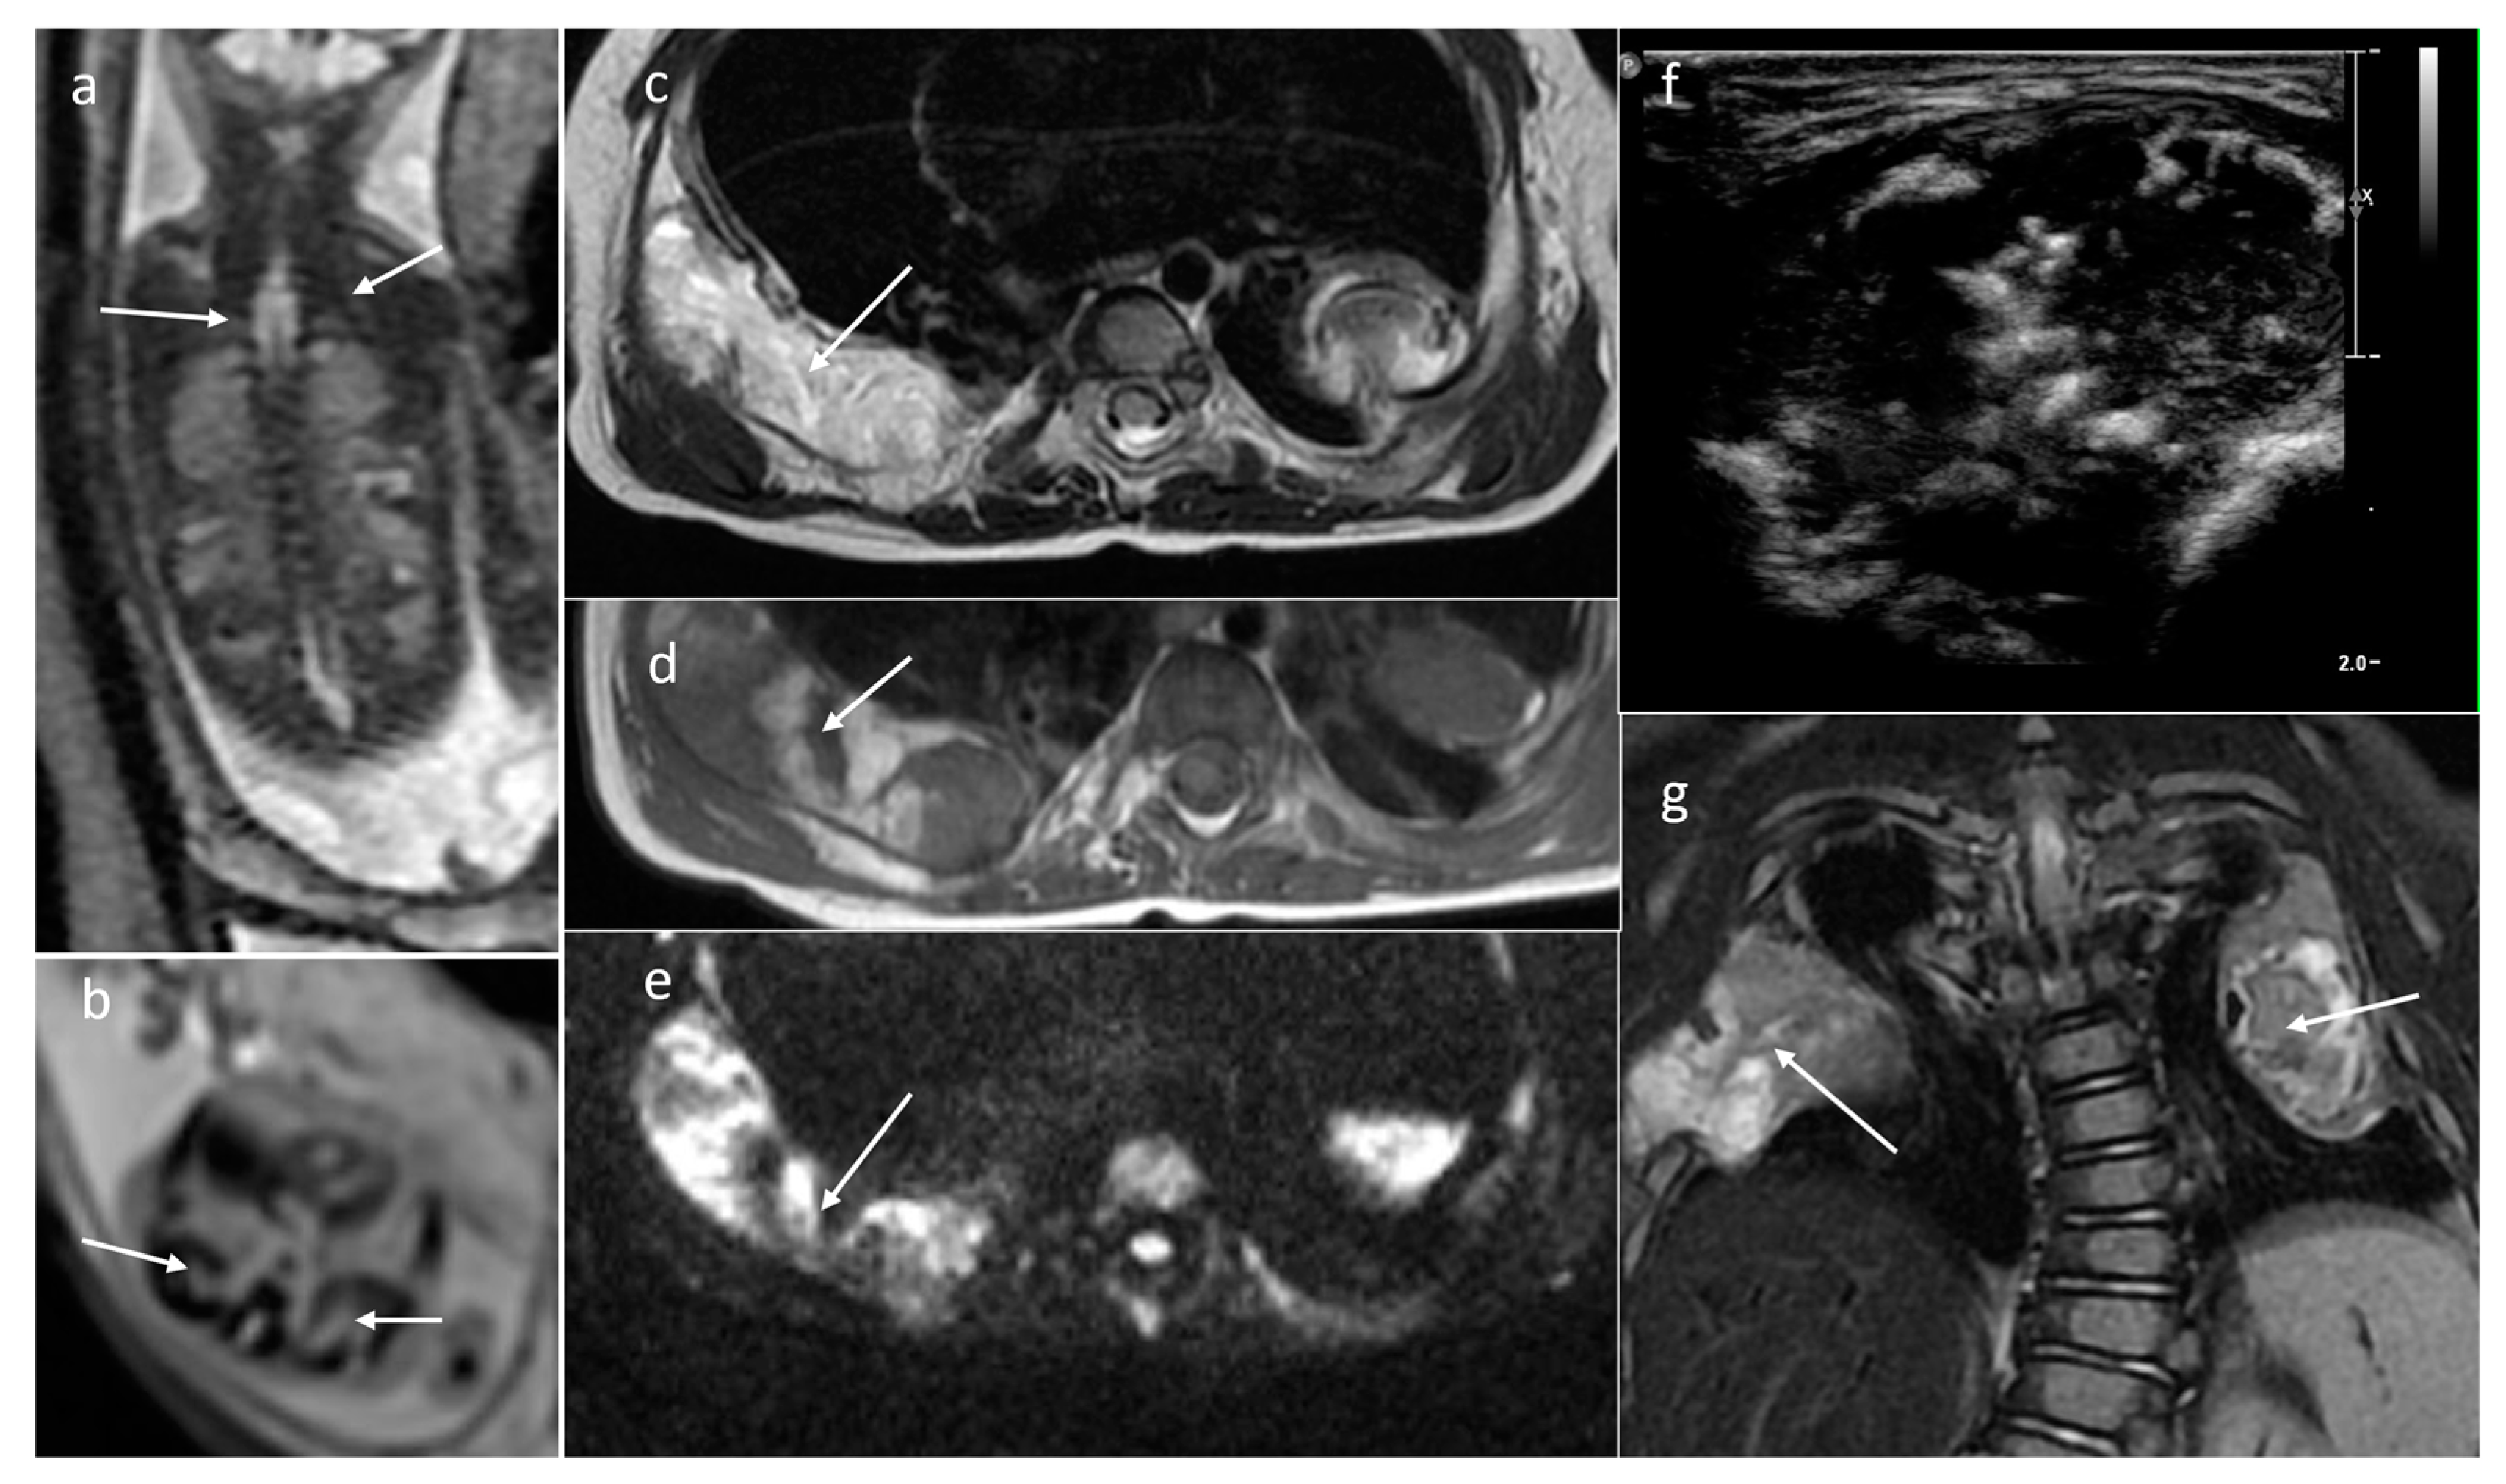

| Neuroblastoma | adrenal gland/infrarenal space | 5 | 11.9 [2.6–24.2] | yes (3/5) (754–1200) | solid/mixed | yes (2/5) | yes (3/3) |

| Infantile fibrosarcoma | soft tissues of the back | 2 | 235 [47–423] | yes (2/2) (1025–1030) | solid (1) mixed (1) | yes (1/1) | yes 1/1 |

| Malignant rhabdoid tumor | soft tissues in upper right chest, soft tissues of left arm | 2 | 33.8 [20.5–47] | yes (2/2) (638–791) | Solid | no (0/1) | yes 1/1 |